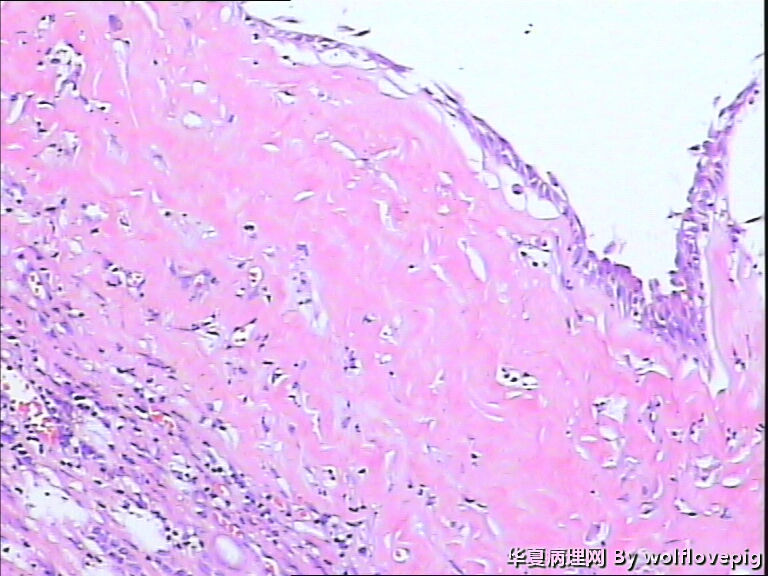

男,70y,左腰痛一年,反复血尿1月,坐肾区轻叩痛。